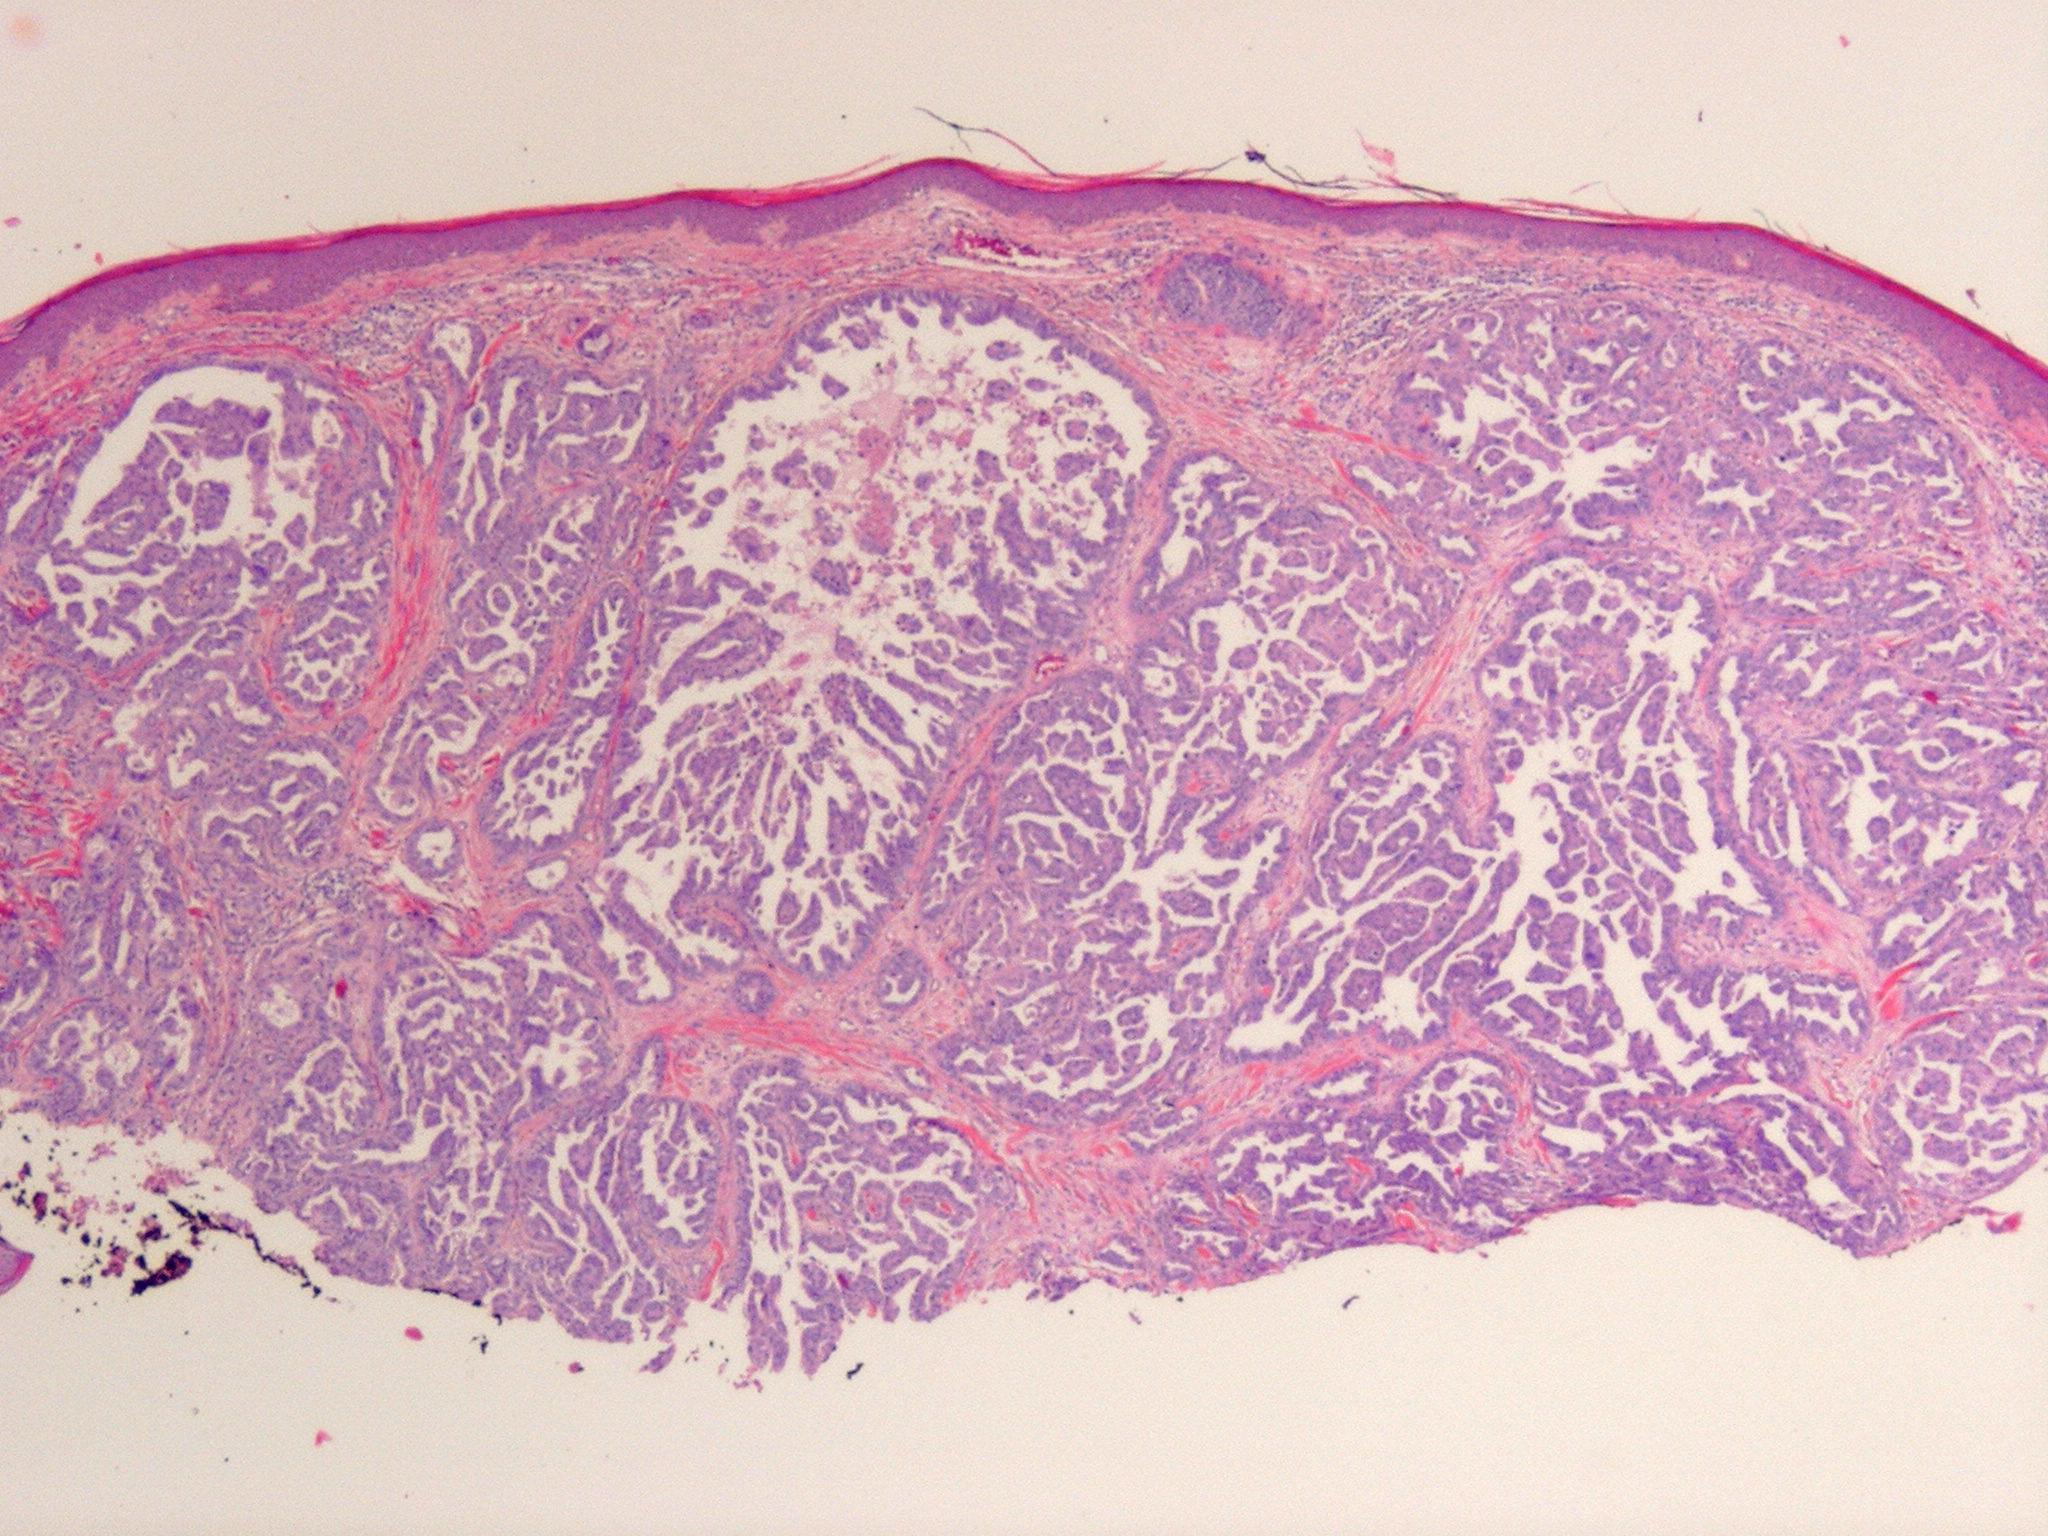

metastasis